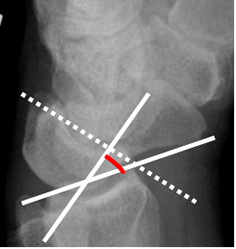

Fig 76. Inestabilidad tipo VISI.

A: Rx lateral. Disminución del ángulo escafolunado, por inestabilidad tipo VISI.